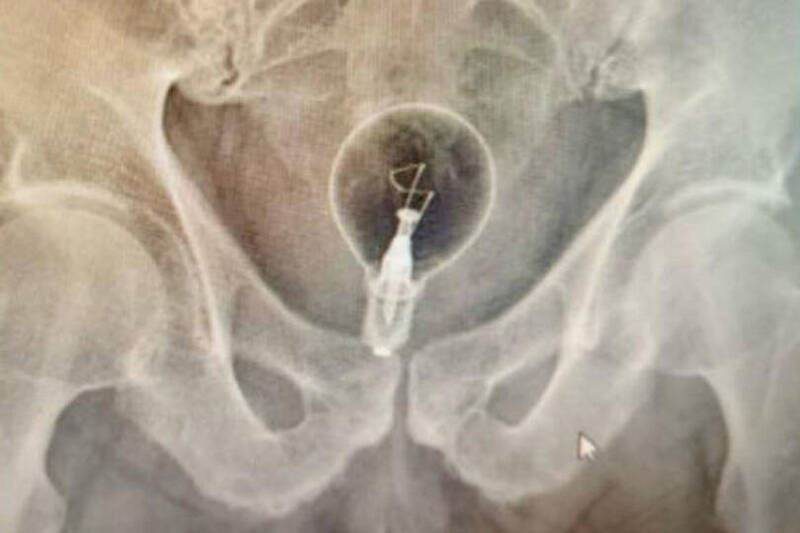

Upon arrival, paramedics immediately transported him to the hospital. An X-ray confirmed the object as an intact light bulb. Surgeons used forceps to carefully remove the bulb without breaking it, minimizing further injury. Due to rectal trauma, the man required hospitalization for observation but was reported to be out of life-threatening danger.